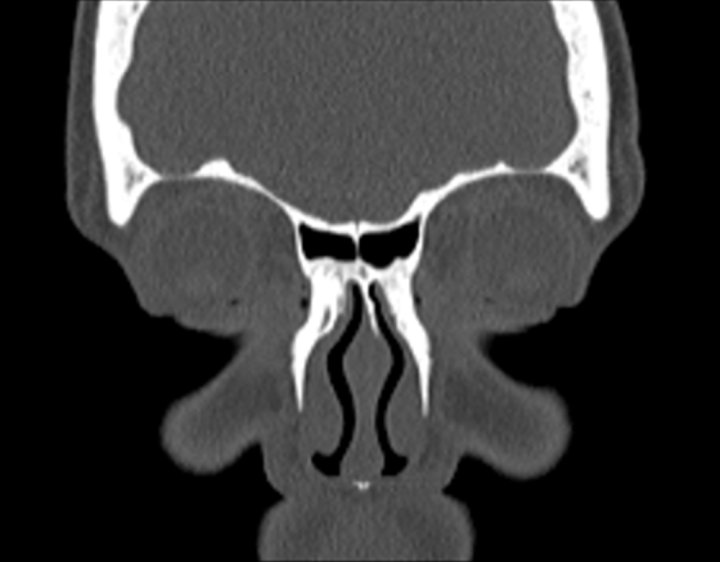

004